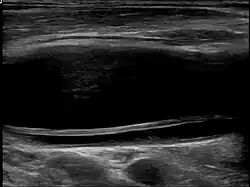

Carotid artery dissection

Dissection of the carotid artery on ultrasound